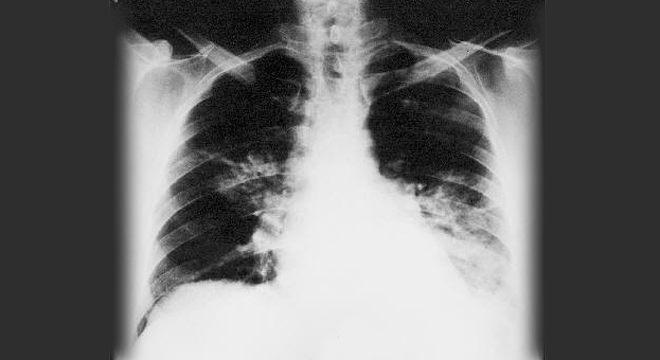

Legionärskrankheit: Röntgenbild der Lungen

• Röntgenbild der Lunge